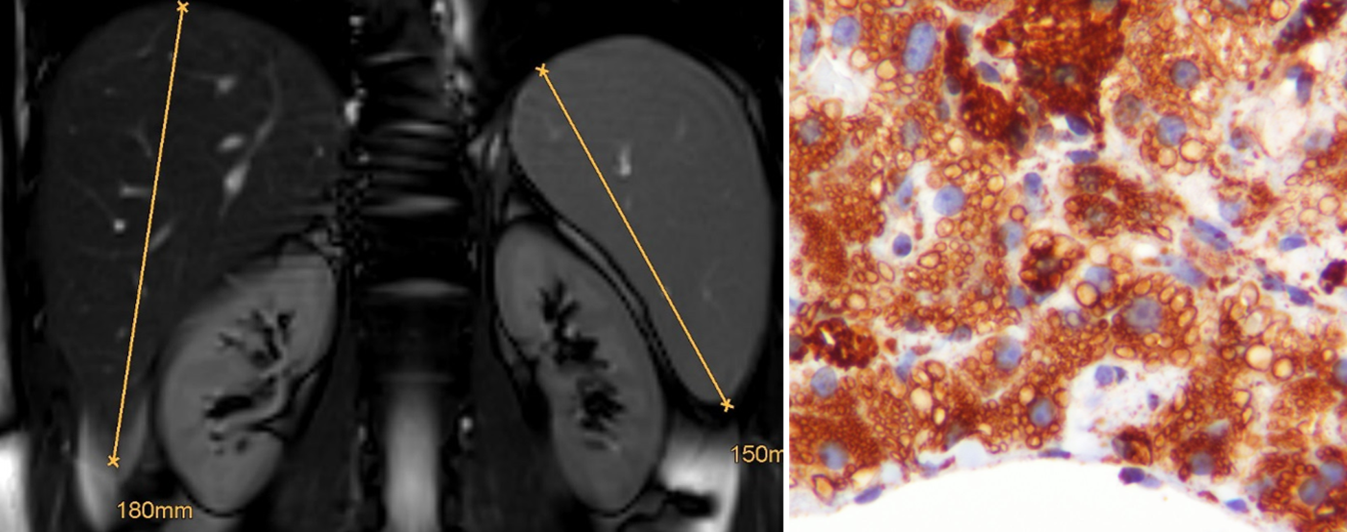

Abb. 2

Knochenmarkbeteiligung bei M. Gaucher bei einer 50-jährigen Patientin und milde Splenomegalie (15,6 cm) bei einem 55-jährigen Patienten: typische Auftreibung der Diaphysen der Femora im Sinne der sog. Erlenmeyerkolbendeformität, die analog zur Entstehung der Hepatosplenomegalie auf der Speicherung von Glukosylzeramid in Makrophagen beruht